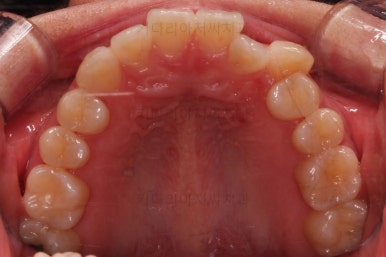

삐뚤한 덧니를 가지런하게 하기 위해서 필요한 부분의 어금니를 순차적으로 뒤로 밀어줍니다.

자세히 보면 치아 사이사이에 틈새가 생기는게 보이죠?

틈새를 일부러 만들어 해당 공간으로 덧니를 가지런하게 하는 원리입니다.

장치를 사용한지 1년 2개월째 사진입니다.

매우 가지런해졌죠.